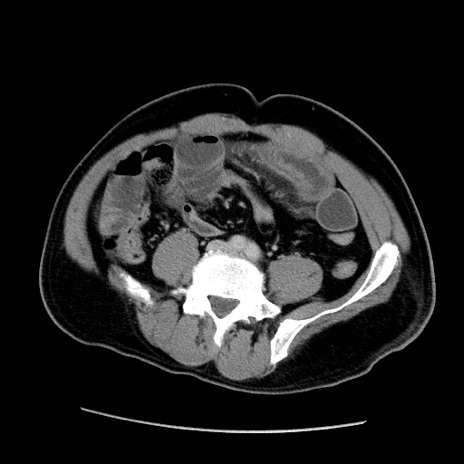

症例22(横断像)

【症例】50歳代男性

【主訴】腹痛

【現病歴】AVMからの被殻出血のため回復期リハ病棟入院中。 本日午後3時頃急に下腹部痛が出現した。

【既往歴】AVM、被殻出血、虫垂炎、高血圧

【身体所見】意識晴明、左半身不全麻痺、会話の理解は良好、36.5°C、腹部:膨隆、全体に板状硬、下腹部正中に圧痛点あり、反跳痛-、筋性防御不明、右下腹部にope scar

【データ】WBC 9400、CRP 0.06